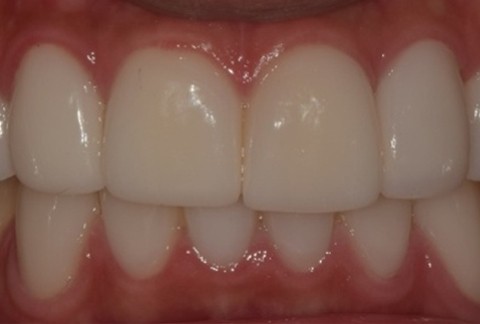

임플란트-전후사진